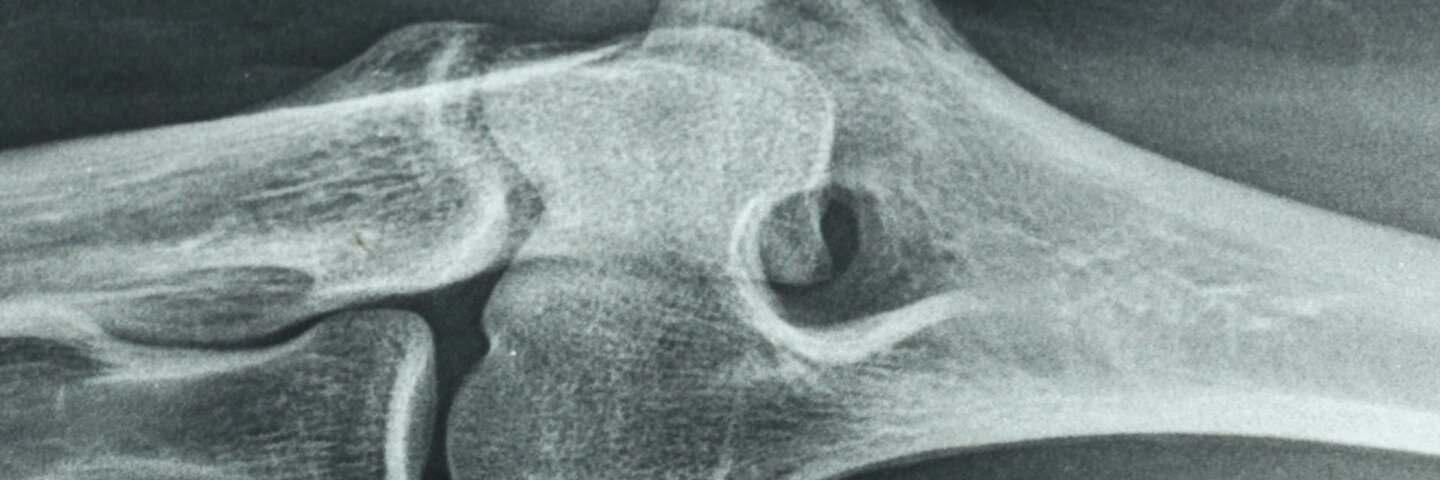

This course addresses the ontogenesis of the osteoimmune processes and discusses bone pathologies that involve immune responses, such as osteoarthritis, osteoporosis, and osteonecrosis through the normal human life span. The interactive curriculum includes a balanced mix of lectures; individual performance; group work; and online discussion on the subject of the interaction and interconnectivity between bone, immune biology, and certain pathological states. Basic courses in human physiology and immunology are recommended prerequisites.